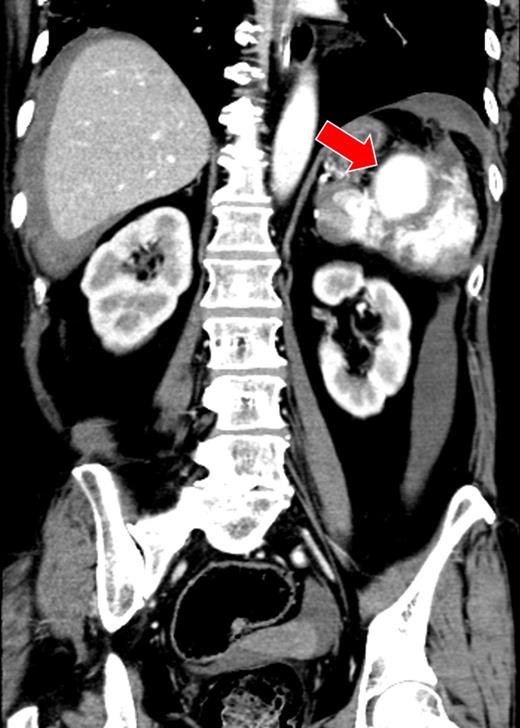

A 66-year-old man presented after suffering sudden hypotension and abdominal distension, followed by a rapid and progressive anemia. After arriving at hospital, he collapsed and went into cardiac arrest. Return of spontaneous circulation occurred after 36 min of cardiopulmonary resuscitation and rapid blood transfusion. Abdominal contrast-enhanced computed tomography (CECT) revealed a large hematoma around the spleen and liver, in paracolic gutters and the pelvis with active arterial extravasation and apparent capsular disruption (Fig. 1). He was transferred to our hospital for definitive, emergency hemostasis. At admission, his systolic blood pressure (BP) was 90 mmHg; heart rate (HR), 80 bpm; hemoglobin (Hb) level, 6.7 g/dl; hematocrit (Ht), 19.0%; prothrombin time-international normalized ratio (PT-INR), 2.16 and activated partial thromboplastin time (APTT), 63.9 s (under massive transfusion). He was currently on warfarin therapy for anticoagulation following a total aortic arch replacement including aortic valve replacement at the age of 60. He presented with no history of trauma, and Moraxella catarrhalis had been detected in a blood culture taken on initial presentation. We made a diagnosis of ASR secondary to infection exacerbated by anticoagulation therapy. We first planned to perform a splenectomy as a definitive hemostatic treatment. However, his transfusion requirement was massive and the risk of significantly worsened hemorrhage during any operative procedure was increased by his iatrogenic coagulopathy. After discussion with surgery team and interventional radiology (IR) team, transient occlusion of the splenic artery using a microballoon catheter was performed (LOGOS, Piolax, Inc., Kanagawa, Japan; arrival to occlusion, 90 min; arrival to angiography suite, 60 min; procedure time to occlusion, 15 min; Fig. 2). Soon after balloon occlusion, the patient's hemodynamic state improved and his anemia stabilized. Perioperatively, 6 units of red cell concentrate (RCC) and 10 units of fresh frozen plasma (FFP) were transfused. The patient's coagulopathy improved on hospital Day 2 (Ht, 25%; PT-INR, 1.35 and APTT, 33.5 s) and was taken to the operating theater for open splenectomy. The spleen was swollen and capsular rupture was indeed identified, but there was no finding of a solid tumor or abscess formation. Bone marrow aspiration did not reveal any evidence of a hematological disorder. There was no subsequent hemorrhage postoperatively. He was extubated on Day 4, and was discharged from the ICU on Day 6. The patient was transferred to another hospital on Day 25 without residual deficits or complications from his cardiac arrest.

There was a massive hematoma in the peritoneum surrounding the spleen and the liver, and extending into the paracolic gutter and the pelvic cavity. The capsule of the spleen was disrupted, and active arterial extravasation can be seen around the spleen (arrow).